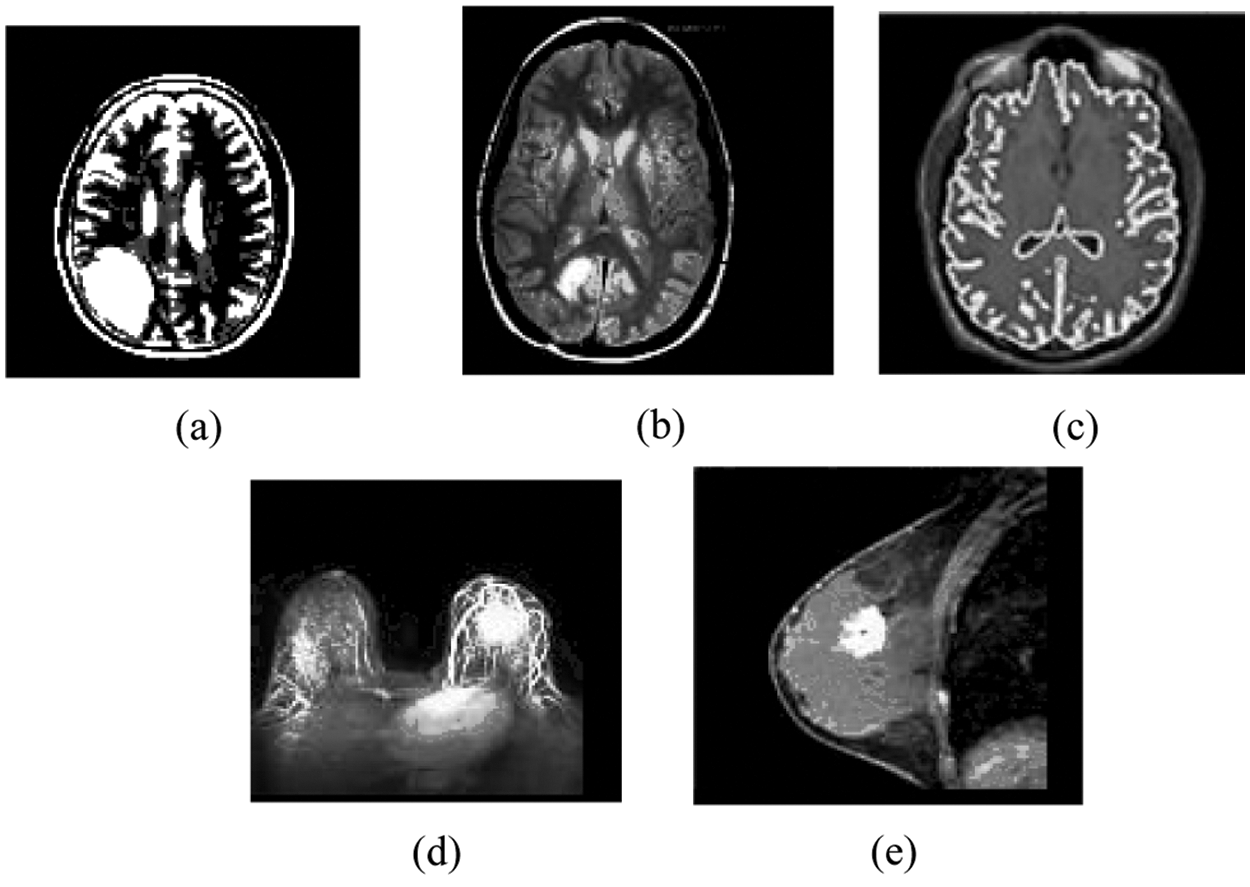

Figure 4: Result of the MIPC scheme tested on the ten MR images using DAAC approach indicated in Fig. 2: (a) Result of brain_1 (b) Result of brain_2 (c) Result of brain_3 (d) Result of breast_1 (e) Result of breast_2

In the same way, the MIPC approach divides the MR image dataset into distinct number of discrete clusters based on ONM scheme. In the beginning, it robotically traces the distinct number spatial centroid objects on each individual gray scale MR image dataset based on control centroid (CC = 15) and the results are incorporated in Tab. 3. The Control Centroid (CC) is a user defined threshold that is used to generate the spatial centroid objects in dataset dynamically. Then it followed by iterative process and divides the each individual image dataset into distinct number of dissimilar clusters based on spatial centroid objects as presented in Tab. 3. The resulting clusters of the five gray scale MR images are incorporated in the Tab. 3. Fig. 4 demonstrates the clustering result of the MIPC (ONM) on five gray scale medical images Brain_1, Brain_2, Brain_3, Breast_1 and Breast_2 as obtained in Figs. 4a–4e respectively.